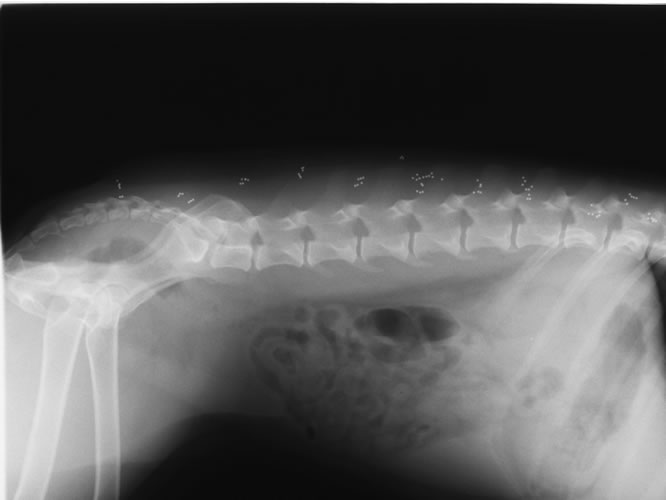

This picture is an x-ray of Korie taken several months after the gold bead implants. She is laying on her back and you can see her tail at the bottom of the x-ray. The small dots along the spine area are the gold beads.